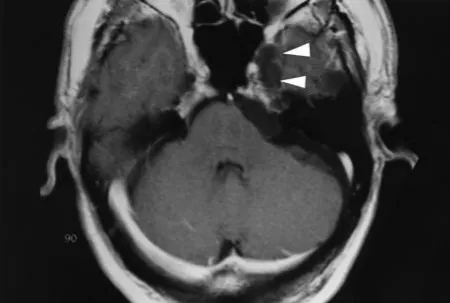

这是一个位于左侧桥小脑角(CPA)区和Meckel腔的表皮样囊肿。

轴位T1加权图像显示稍高信号病灶伴占位效应;箭头指示Meckel腔内的肿瘤。

轴位CISS图像显示内听道前方和Meckel腔内的稍低信号病灶(箭头指示)。

磁共振成像是检测表皮样囊肿的首选诊断方法。然而,蛛网膜囊肿和表皮样囊肿的鉴别有时仍然困难。在标准T1和T2加权自旋回波MR图像上,表皮样囊肿常难以与脑脊液区分;因此,已研究了其他成像序列。液体衰减反转恢复成像、弥散加权成像和CISS序列已被推荐用于表皮样囊肿的特征化。根据施罗德教授的经验,CISS是检测表皮样囊肿的最佳序列;CISS成像可以清晰区分脑脊液,并准确显示病变范围。在CISS图像上,表皮样囊肿通常表现为不均匀、低信号、边界不规则的结构。尽管大多数表皮样囊肿在T1加权图像上相对于脑脊液呈稍高信号,但CISS序列能更清晰地显示这些病变。